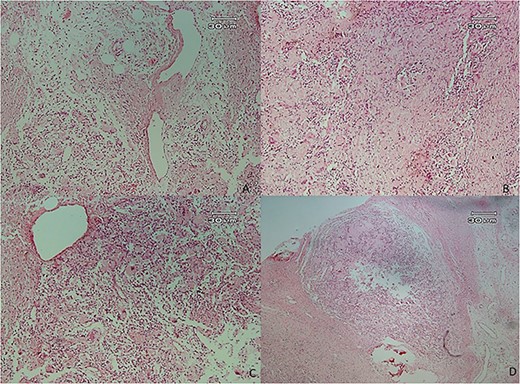

Microscopic examination showed (Figs 4–7) inflamed connective tissue composed of prominent plasma cells mixed with numerous osteoclastic multinucleated giant cells of various sizes with intracytoplasmic asteroid bodies and round Schaumann bodies, which surrounding round to amorphous eosinophilic areas composed of the spindle to stellate cells in fibromyxoid background is also evident.

Histopathologic views of the lesion (H&E staining, ×100 magnification). (A) Inflamed fibromyxoid connective tissue. (B) Area of one granulomatous pattern inflammation with multiple giant cells. (C) Numerous foreign body giant cells admixed with severe chronic.

Histopathologic views of the lesion (H&E staining, ×10 magnification). Inflammation in the connective tissue and foreign body giant cells admixed with severe chronic inflammatory cells.

Histopathologic views of the lesion (H&E staining, ×100 magnification). Inflamed fibromyxoid connective tissue and foreign body giant cells.

Histopathologic views of the lesion (H&E staining×100 magnification) showing chronic inflammatory cells admixed with multinucleated giant cells of varying sizes.